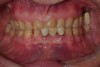

Figure 4  Inter-occlusal registration made at the approximate OVD for rehabilitation.

Figure 4